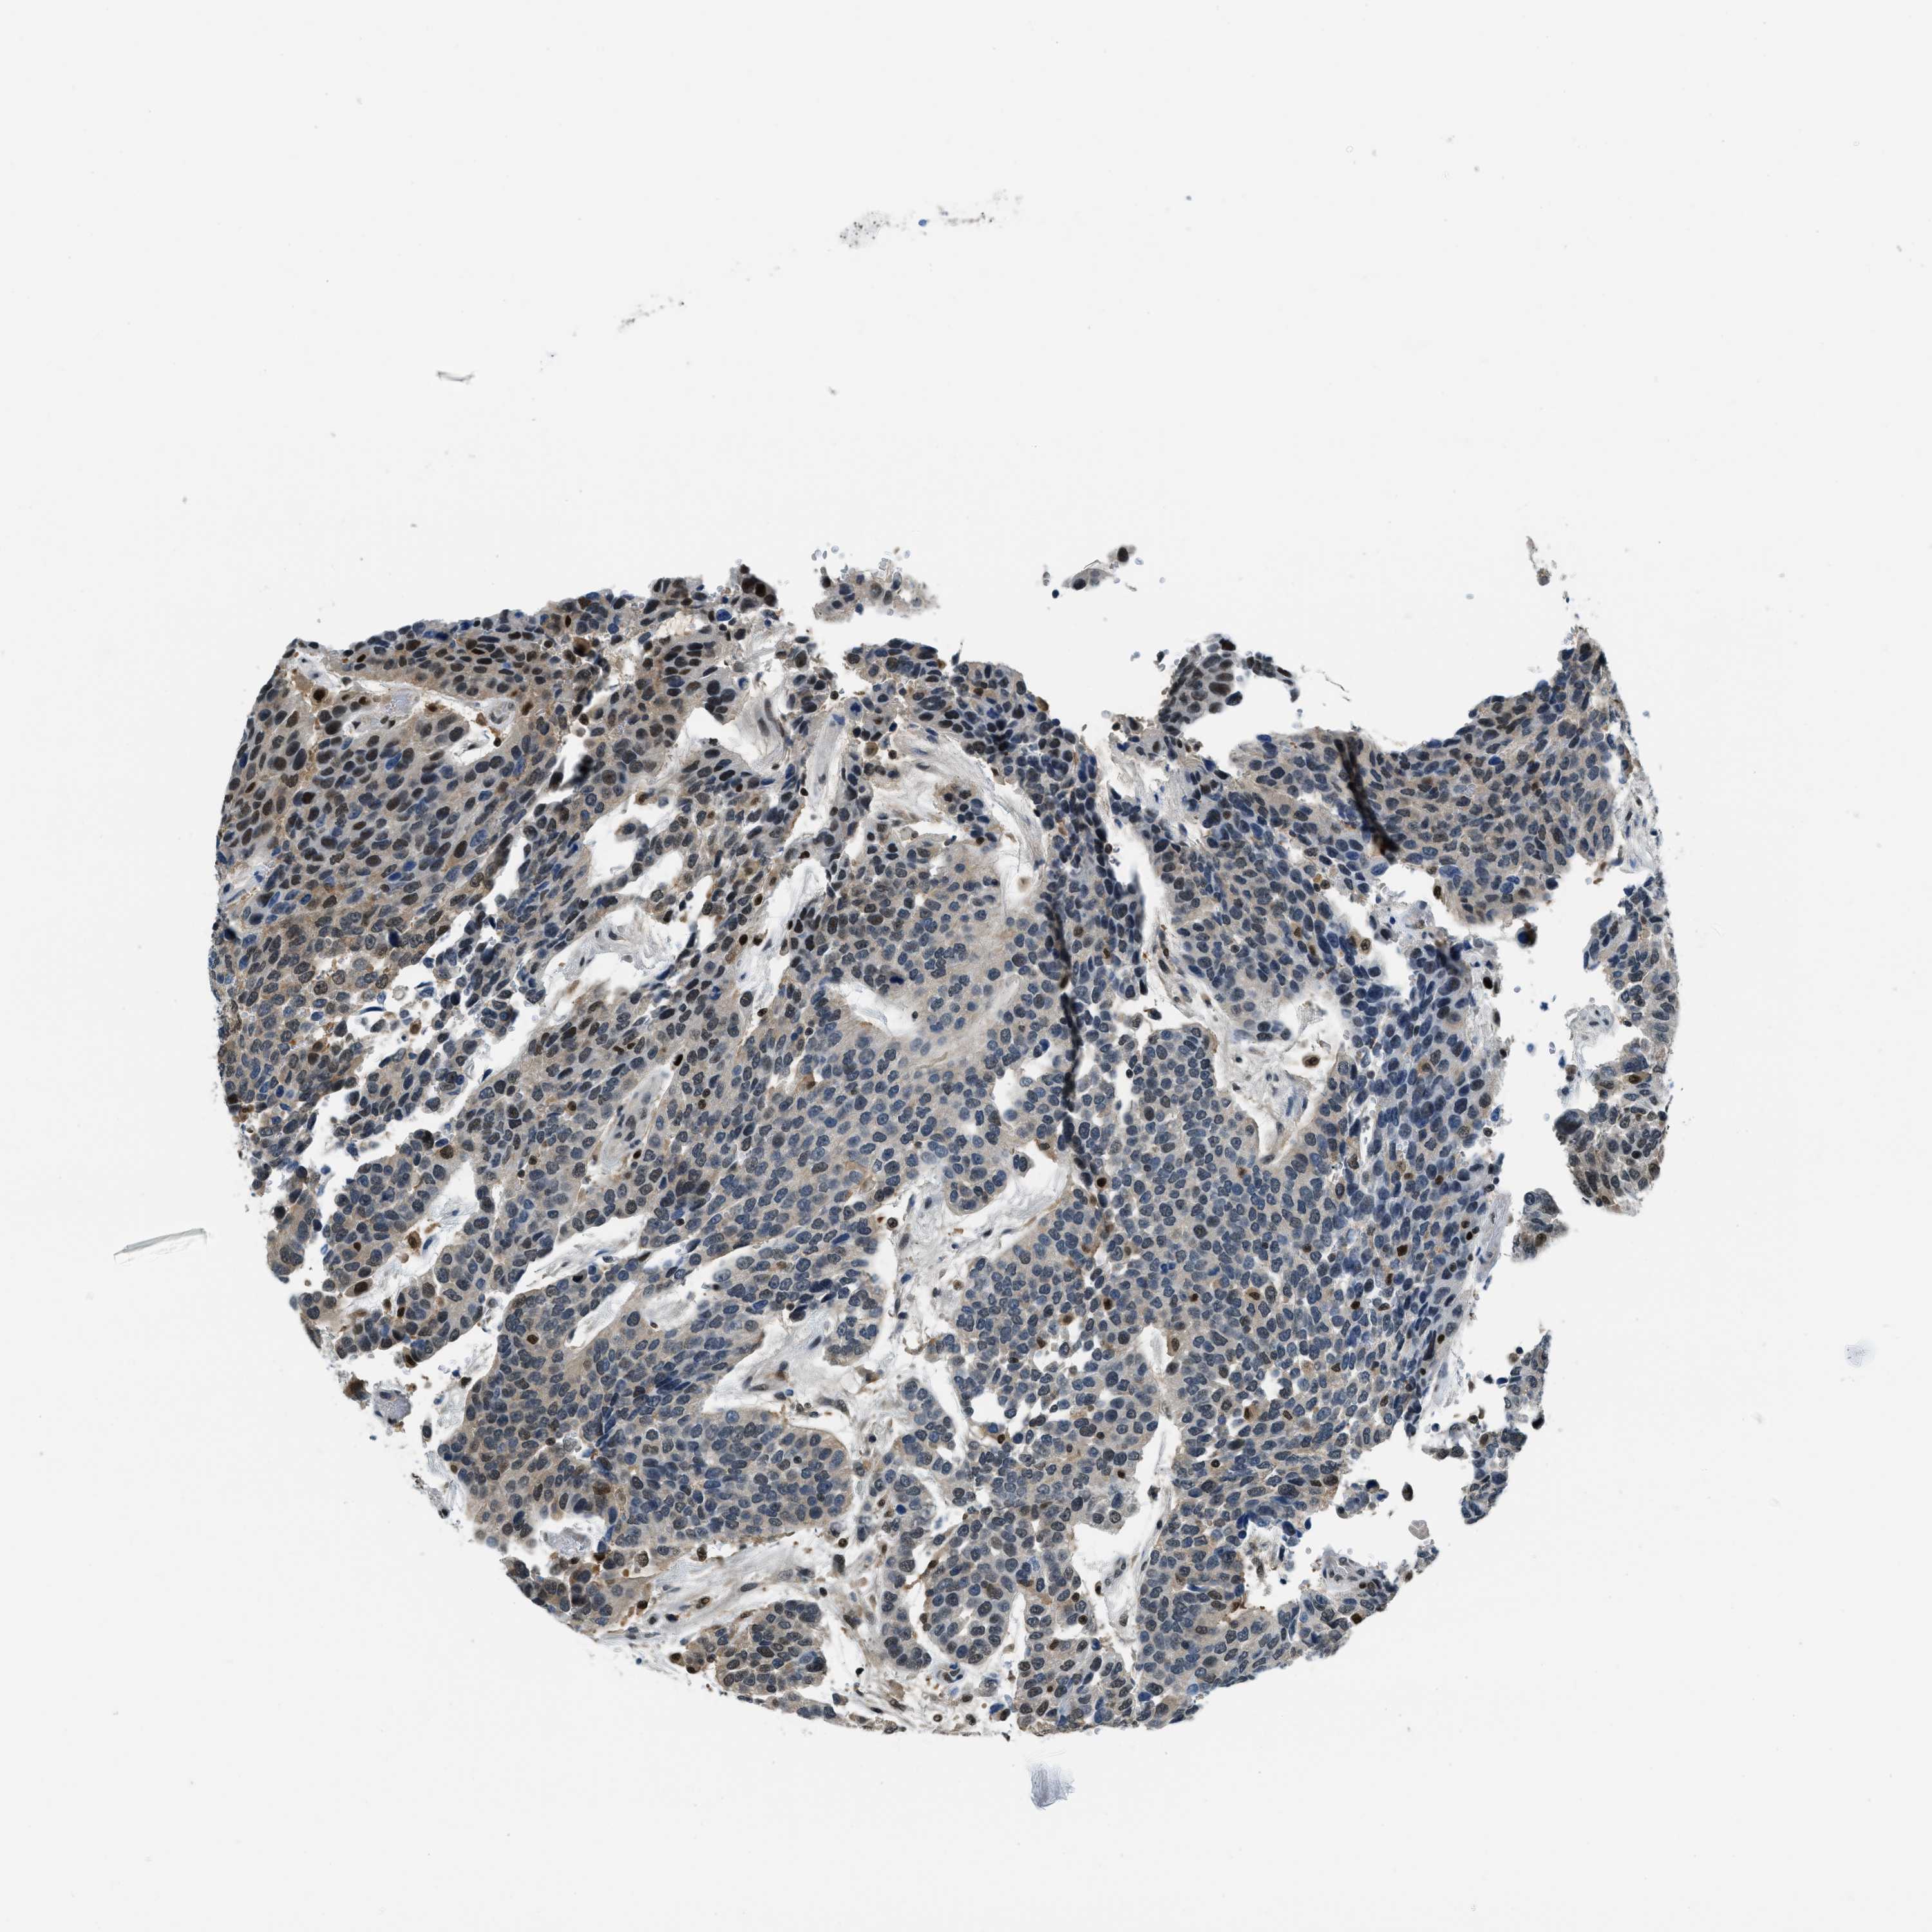

UROTHELIAL CANCER - Protein expressioni

A mouse-over function shows sample information and annotation data. Click on an image to view it in a full screen mode. Samples can be filtered based on level of antibody staining by selecting one or several of the following categories: high, medium, low and not detected. The assay and annotation is described here.

Note that samples used for immunohistochemistry by the Human Protein Atlas do not correspond to samples in the TCGA dataset.

Antibody stainingi

Antibody staining in the annotated cell types in the current human tissue is reported as not detected, low, medium, or high, based on conventional immunohistochemistry profiling in selected tissues. This score is based on the combination of the staining intensity and fraction of stained cells.

Each image is clickable and will lead to virtual microscopy that enables deeper exploration of all samples and also displays staining intensity scores, fraction scores and subcellular localization as well as patient and tissue information for each sample.

Antibody HPA017899

Staining

High

Medium

Low

Not detected

Intensity

Strong

Moderate

Weak

Negative

Quantity

>75%

75%-25%

<25%

None

Location

Urothelial carcinoma, Low grade

Urothelial carcinoma, High grade